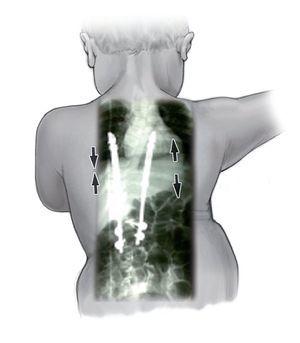

La indicación para la intervención fue en 16 casos una escoliosis congénita (figs. 24a-24c), en once casos una escoliosis neurológica y en doce casos una EIP. Las curvas se determinaron según Cobb. El ángulo de Cobb antes de la intervención medía un promedio de 65º (45-130º), y después de la intervención, un promedio de 32º (25-75º). En 18 pacientes tratamos una escoliosis torácica, en 18 pacientes una toracolumbar y en tres pacientes una lumbar (mielomeningocele). En 18 casos se utilizó un implante «costilla a costilla», en cinco casos un sistema de barra doble hasta la pelvis y en 18 casos un sistema híbrido (figs. 25 y 26).

Figuras 25a a 25c. a) Radiografía preoperatoria en proyección anteroposterior de una EIP con un ángulo de Cobb de 86º. b) Radiografía postoperatoria de una instrumentación «costilla a CL» realizada en una escoliosis toracolumbar progresiva. c) Radiografía postoperatoria en proyección anteroposterior después de 5 años. La curva se mantiene flexible y con buena corrección.

Realizamos un total de 39 implantes primarios, 102 cirugías de expansión y 24 sustituciones de implante. Estas últimas fueron necesarias debido a la aparición de curvas compensatorias o porque los implantes se habían quedado pequeños como consecuencia del crecimiento. Cada niño fue intervenido entre una y nueve veces (figs. 25a a 25c).